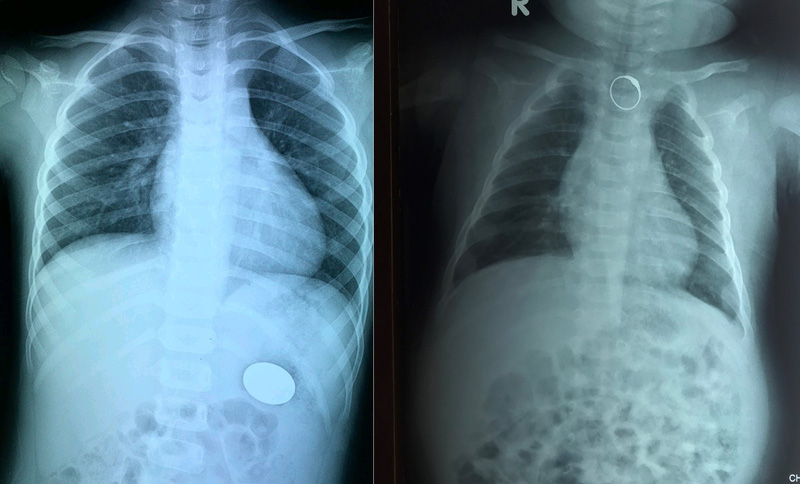

Tại bệnh viện, sau thăm khám và kết quả chụp X-quang, các bác sĩ xác định có hình ảnh dị vật dạng kim loại giống chiếc nhẫn nằm trong thực quản đoạn thực quản ngực của bệnh nhi.

Qua kết quả X-quang cho thấy, có dị vật cản quang dạng đồng xu trong ống tiêu hóa bên trái ngang mức cung sau xương sườn D12. Ngay sau đó, bệnh nhi được gắp dị vật đồng xu khỏi dạ dày.